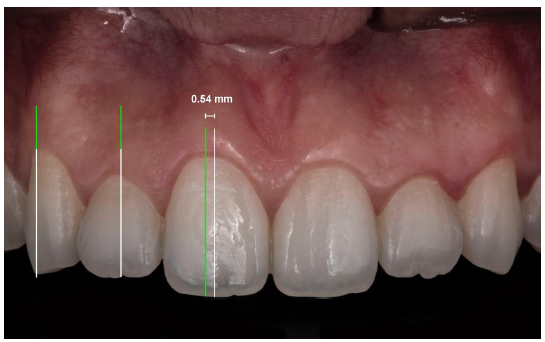

Al cuantificar la distancia en el que se ubica el cenit con respecto al eje longitudinal, se encontró que fue de 0,54 mm hacia distal en incisivos centrales (tabla 3), y 0 mm en los incisivos laterales y caninos superiores (figura 2). No se encontró relación entre la distancia del cénit al eje longitudinal con el género (tabla 4) y, asimismo, con el grupo etario (tabla 5).

Con respecto a la ubicación de cénit gingival en los incisivos centrales superiores, en el 72,8% de la muestra se halló que se ubicaba hacia distal. Al cuantificar la distancia con respecto al eje longitudinal se obtuvo una media de 0,54mm. Estudios realizados por Chu y col., (21), Nappe y col., (13), y Vera (14) hallaron resultados similares, pero con una marcada diferencia con respecto a la distancia obtenida por Chu y col., que fue de 1 mm a distal (12), Nappe y col., fue de 1,419 mm (13), y de Vera fue de 0,89 mm (14). Esta diferencia en las longitudes puede ser consecuencia a la realización del estudio en diferentes poblaciones y diferentes grupos etarios.